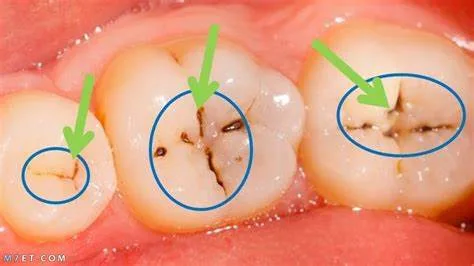

تسوس الأسنان هو مشكلة شائعة تواجه الناس من جميع الأعمار، ويمكن أن يسبب آلماً شديداً ويؤثر على مظهر الأسنان. قد يتسبب التسوس أيضاً في عدم القدرة على تناول بعض الأطعمة. في هذا الموقع“إيجي بلوج نيوز”، سنعرض طرق علاج تسوس الأسنان.

من الضروري إجراء فحوصات دورية على الأسنان لكشف التسوس قبل أن يتفاقم، حيث يمكن أن ينتشر التسوس دون ظهور أي أعراض. يفضل استخدام معجون الأسنان الذي يحتوي على الفلورايد لتقوية المينا ومنع التسوس، ويجب استخدامه مرتين يومياً. هناك العديد من الطرق التي يمكن اتباعها في المنزل للوقاية من التسوس، وسوف نناقش طرق العلاج في البيت فيما يلي:

يجب أن تتضمن العناية بالأسنان توصيات من طبيب الأسنان، مثل استخدام فرشاة الأسنان والمعجون المحتوي على الفلورايد، والكشف المبكر عن تسوس الأسنان لاتخاذ الإجراءات الوقائية المناسبة مثل تركيب التاج أو الحشو.

في النهاية لقد عرضنا أكثر من طريقة طبيعية لعلاج تسوس الأسنان، ولكن يجب أيضا الذهاب إلى دكتور الأسنان لكي يكتشف التسوس مبكراً، ويتم علاج بطريقة أسرع قبل أن ينتشر.